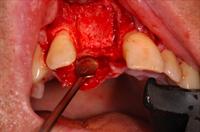

![]() 3. Osteo-Biol Putty |

![]() 4. The ridge split was approxinmately 7mm. This was filled with Osteo-Biol Putty before an Evolution membrane was placed over the area. |